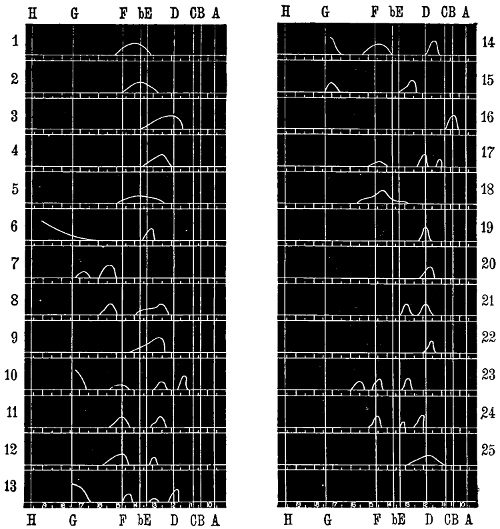

| Diagram showing Absorption Bands Produced from Colour Reactions, | 55 | |

| Diagram of Visual Field in Dinitro-benzol Poisoning, | 190 | |